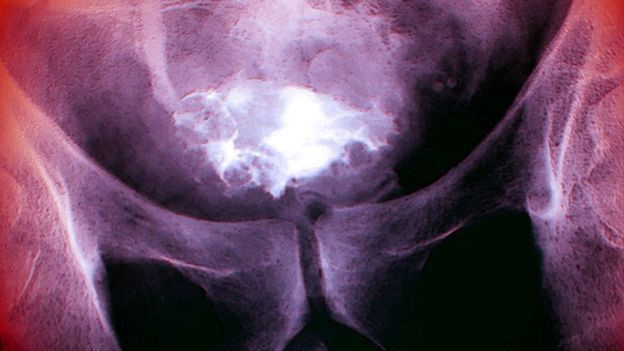

Nhóm nghiên cứu đã tiến hành thử nghiệm lên 15 bệnh nhân được chẩn đoán mắc chứng ung thư bàng quang. Các bệnh nhân sẽ được cấy vào cơ thể một loại virus gây cảm lạnh coxsackievirus (CVA21) một tuần trước khi thực hiện phẫu thuật cắt bỏ khối u.

Kiểm tra mẫu vật khối u, các nhà khoa học phát hiện virus này đã truy tìm và triệt tiêu một số tế bào ung thư trong bàng quang của người bệnh.

Ngay khi tiêu diệt những tế bào này, con virus tự động sản sinh và lây nhiễm vào những tế bào ung thư khác. Bên cạnh đó, loại virus này không hề tác động đến các tế bào khỏe mạnh.